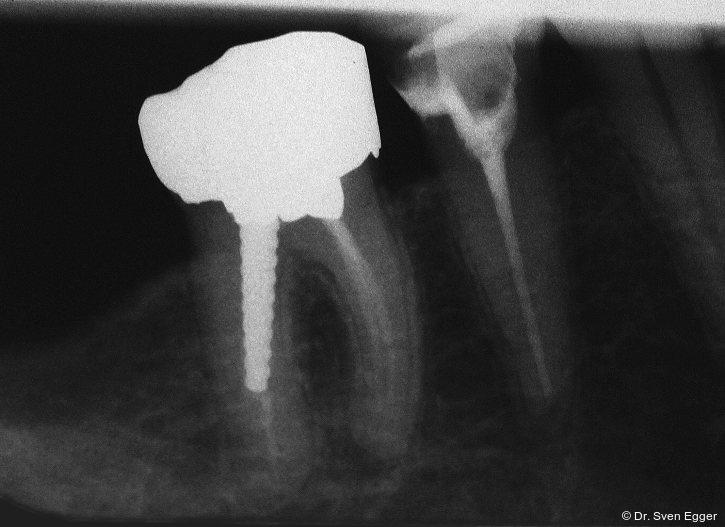

Die mit einem Restrisiko behafteten Zähne 15 und 46 (Zahn 15 zeigte nach Revision noch immer eine leichte Drucksymptomatik, bei Zahn 46 waren die mesialen Wurzelkanäle obliteriert) erwiesen sich in der Vorbehandlung dann als nicht erhaltungswürdig und wurden nach Extraktion durch Einzelzahnimplantate ersetzt. Alternativ hätte im 1. Quadranten die Schaltlücke Regio 15 mit einer festsitzenden Brücke geschlossen werden können. Aufgrund des ausreichenden Knochenangebotes und der besseren Mundhygienefähigkeit entschied sich die Patientin jedoch für den implantatgetragenen Einzelzahnersatz. Eine herausnehmbare Versorgung lehnte die Patientin bereits im Vorfeld ab. Die Schaltlücke im 3. Quadranten konnte im Rahmen der prothetisch/funktionellen Rehabilitation in ZKP belassen werden, da eine Antagonistenabstützung an 26 mesial und distal realisiert werden konnte. Alternativ wäre eine kieferorthopädische Distalisierung (Lückenöffnung) mit Einzelzahnimplantat 036 denkbar gewesen. Der erhöhte Behandlungs- und Zeitaufwand stand aus Sicht des Behandlers jedoch nicht im Verhältnis mit dem daraus resultierenden Nutzen. Einem regelmäßigen Recall steht die Patientin sehr aufgeschlossen gegenüber.

Die Follow-up-Untersuchung zeigte ein Ergebnis, mit dem die Patientin nach 15 Jahren Tragezeit weiterhin vollumfänglich zufrieden ist. Die keramische Teilkrone an Zahn 17 wurde am 31.5.2022 aufgrund Debondings nach erneuter Konditionierung wieder eingesetzt. Die Kieferhöhlen sind verschattungsfrei und zeigen keine Anzeichen eines Rezidivs der in 2007 erfolgten Zystenoperation in der rechten Kieferhöhle (Mukozele). Die endodontisch revidierten Zähne 25 und 45 zeigen weder klinisch noch röntgenologisch Auffälligkeiten. Die Stellung der Ober- und Unterkieferfront sowie die in ZKP etablierte horizontale und vertikale Relation des Unterkiefers ist stabil und bereitet keinerlei Schwierigkeiten. Die Implantate weisen klinisch und röntgenologisch schöne Hart- und Weichgewebsverhältnisse auf. Die häusliche Mundhygiene ist sehr gut. Es sind keine Anzeichen einer Funktionsproblematik zu erkennen. Die Michigan-Schiene wurde 2022 erneuert. Für die vorliegende Situation lässt sich damit auch weiterhin eine sehr gute Langzeitprognose aussprechen (Abb. 18–25).